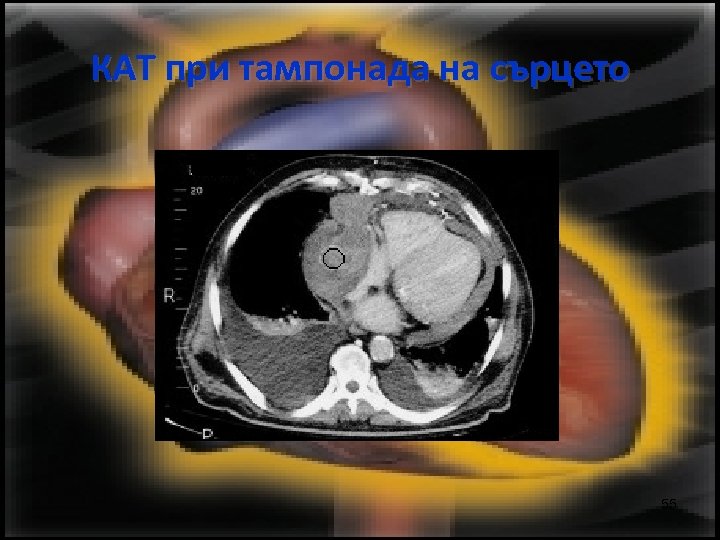

КАТ при тампонада на сърцето 55